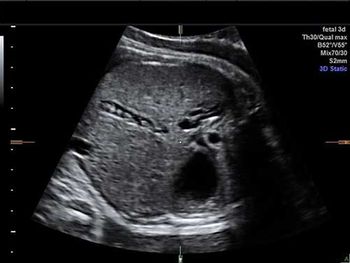

Challenge your diagnostic skills. What's your diagnosis based on these fetal abdominal images?

Challenge your diagnostic skills. What's your diagnosis based on these abdominal images of a late second trimester fetus?